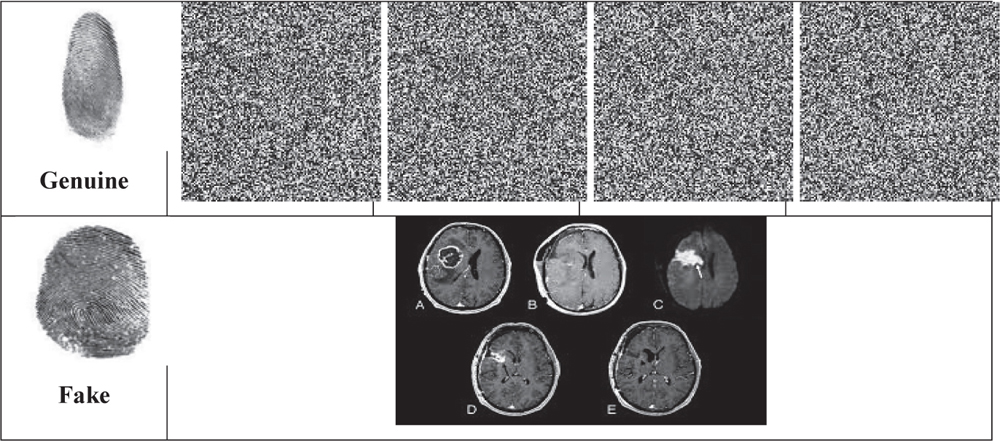

Once the genuine client wants to obtain the secret data, he/she enters the proposed biometric Fingerprint Authentication system, where the finger prints of authenticated users are already enrolled in the finger print template database in hashed format. Based on the matching decision, genuine clients are confirmed and the trusted party decrypts and provides the decrypted shares to them. Here the intermediate results obtained for the proposed Biometric Fingerprint Authentication system is provided in Table 2.

Table 2 Biometric fingerprint authentication results

In Table 2, the first row represents the genuine fingerprint provided by authenticated user receiving decrypted shares. Second row, fake fingerprint is provided and the system giving some random image is given.